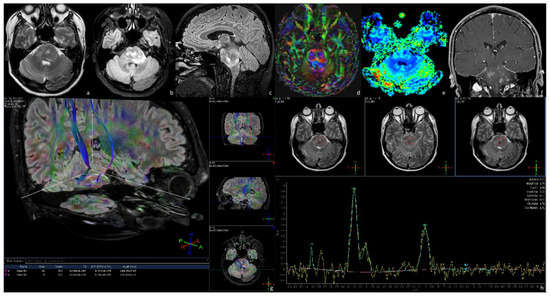

3.4.2. Brainstem Gliomas Associated with Neurofibromatosis Type 1 (NFBSGs)